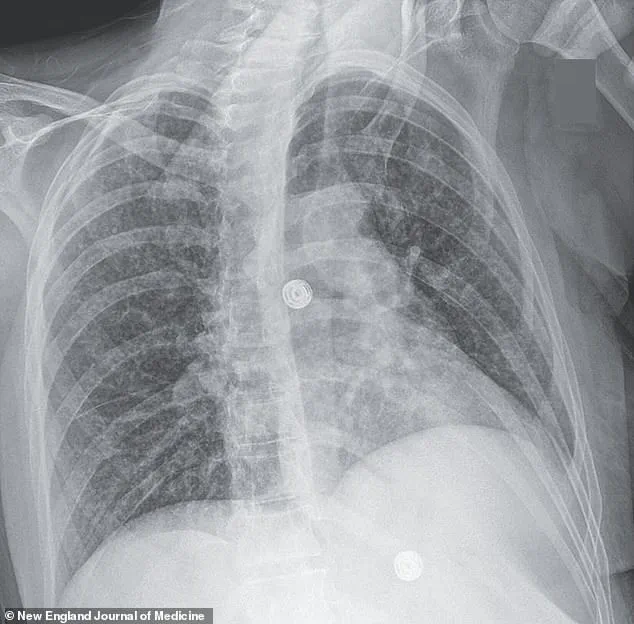

X-ray scans revealed an alarming finding: multiple small nodules scattered across her lungs, a hallmark sign of bacterial infection.

Further imaging and biopsies painted a more sinister picture.

Lesions were detected in her liver, lymph nodes, pancreas, and brain—organs that should have been untouched by the disease.

A recent case study highlights this grim reality: a woman’s scans revealed nodules in her lungs, liver, pancreas, and brain, with an enlarged lymph node in her chest.

These findings, though rare, underscore the disease’s potential to evade detection and wreak havoc on multiple organ systems.